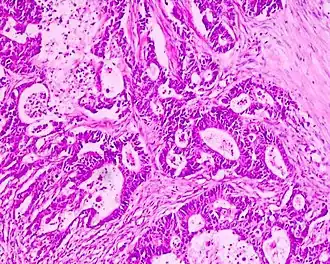

Een adenocarcinoom[2] of klierkanker[2] is een carcinoom dat in het epitheelweefsel van klieren ontstaat. Om als adenocarcinoom te worden gekenmerkt hoeven de cellen niet strikt noodzakelijk deel van een klier uit te maken, zolang de cellen maar een excretiefunctie hebben. Een goedaardige gezwel dat uitgaat van klierweefsel, wordt adenoom genoemd.